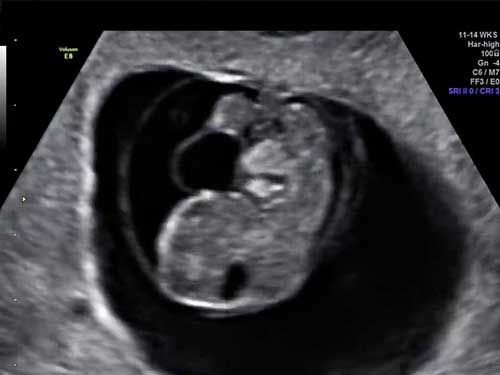

Challenge your diagnostic skills: Do these images depict normal limb growth?